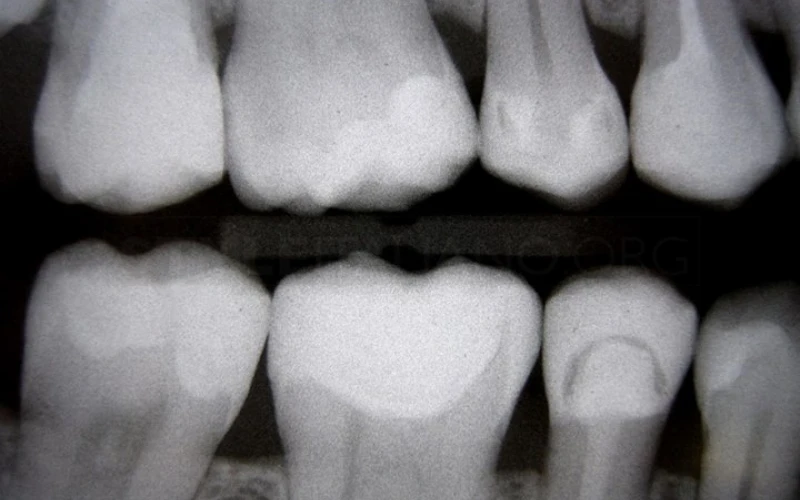

2. Phim cánh cắn cho thấy các răng nguyên nhân.

18. Phim cánh cắn sau điều trị. Tất cả các phục hình đều là composite, trực tiếp hoặc gián tiếp.